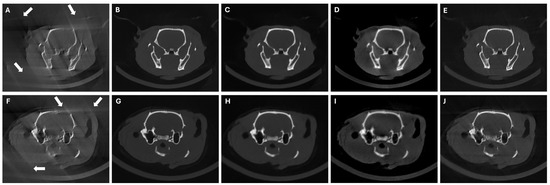

3.4. Results in Highly Limited-Data Scenarios